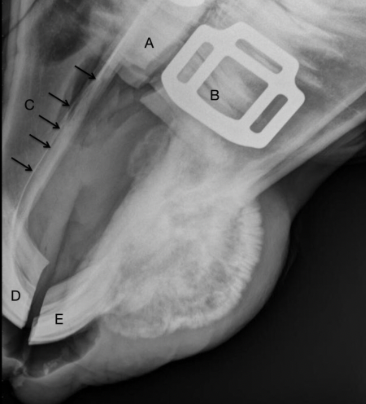

Q

Label the structures

A

A = patella

B = distal femur

C = fabellae

D = tibia

E = fibula